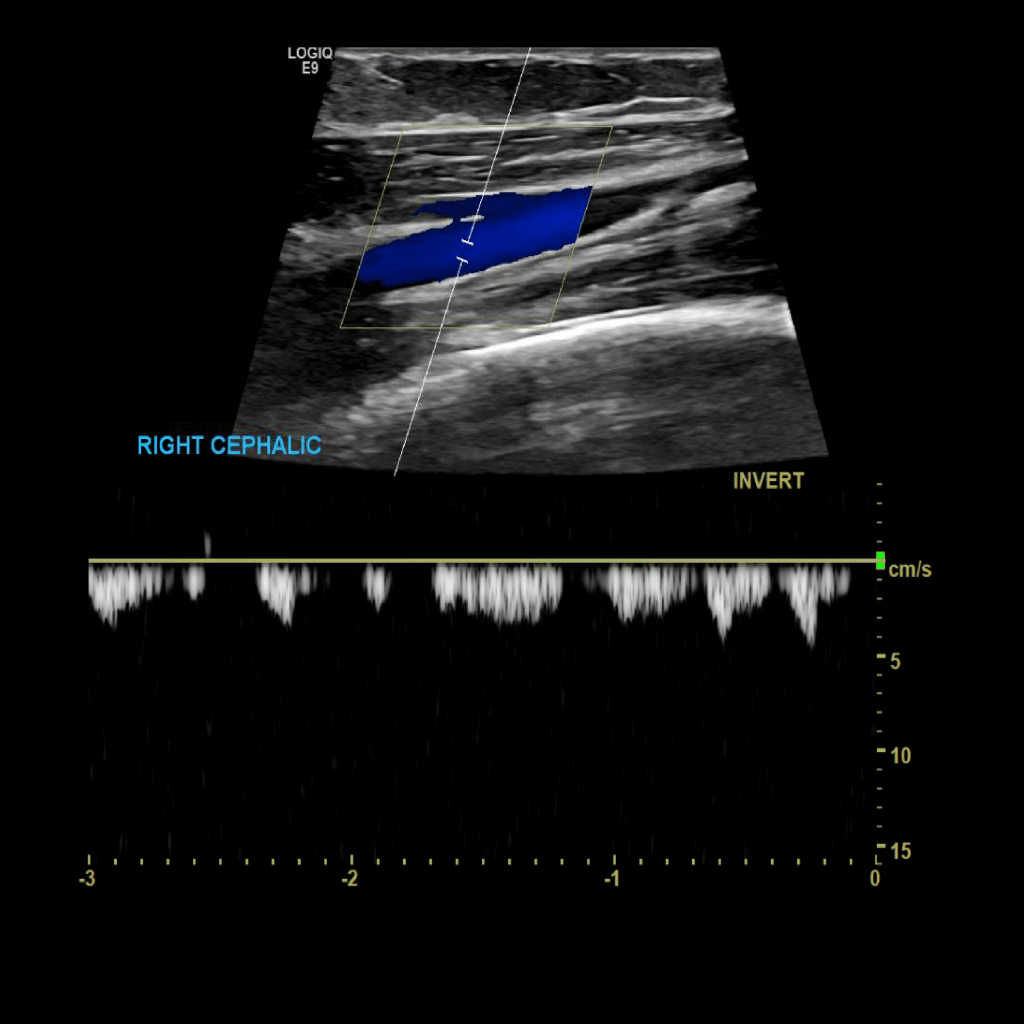

Scan the cephalic vein in grey scale, compression, color doppler and spectral doppler